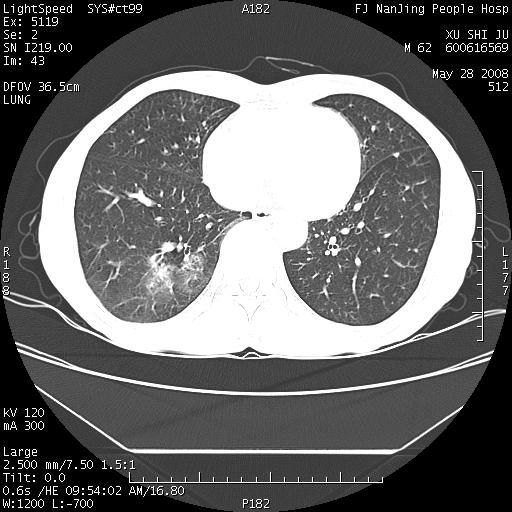

以下是引用杀毒软件在2008-5-28 19:16:00的发言:[br]病灶旁“晕轮征”,考虑肺真菌病

以下是引用qiushi在2008-5-28 20:01:00的发言:[br]空洞周围环状磨玻璃影(日晕征),考虑肺曲霉菌病.

以下是引用yuhongjun在2008-5-29 4:28:00的发言:[br]空洞周围环状磨玻璃影(日晕征),考虑肺曲霉菌病。支持! [br] [br]

以下是引用lrj在2008-5-28 21:10:00的发言:[br]所示应该是正常结构,是对称的,多个层面都有!也不像是内乳动脉或是肿大淋巴结![br]右下肺渗出性病变伴空洞形成,其洞内见一结节,以下诊断都有可能:1 右下肺曲菌感染, 2右下肺结核空洞形成伴曲菌感染!3右下肺结核空洞伴壁内占位形成,虽说后者发生的几率很低 但作为我们应该多考虑一下吧!最重要的结合临床